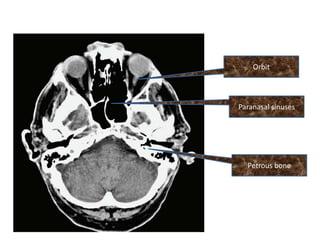

Orbit

Paranasal sinuses

Petrous bone